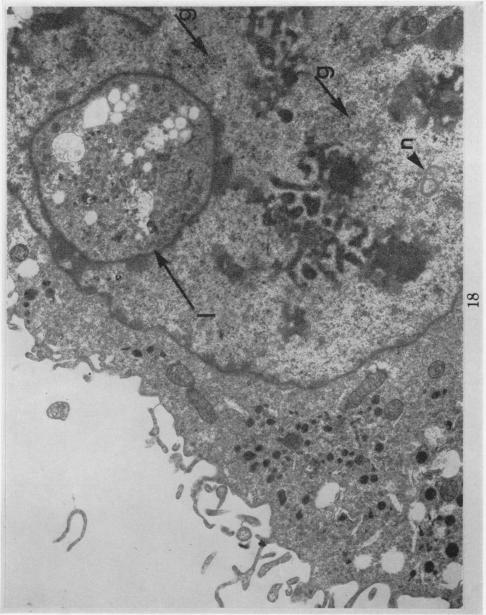

The pleomorphic cytology of the HT-1 cell line is described. Cytochemical studies indicated the presence of glycogen and lysosomes in these cells. Cytogenetic studies demonstrated the presence of a large telocentric chromosome (M1) and two minute chromosomes (M2) not found in normal hamster cells. A cloned line was isolated which did not contain these marker chromosomes. All cells were hyperdiploid with chromosome number around triploidy, although none was a true triploid. Ultrastructural studies revealed the presence of "nuclear bodies", "dense bodies" and "interchromatinic granules" which have been previously described in viral induced malignancies. A few of the cells contained in their cytoplasm structures of approximately 700 [unk] in diameter which bore some resemblance to immature virus particles. Both light and electron microscopy demonstrated some nuclei lacking chromatin aggregates. This is interpreted to mean that the total genetic material of these nuclei was dispersed as free DNA not linked with histone to form chromatin aggregates.

描述了HT - 1细胞系的多形性细胞学特征。细胞化学研究表明这些细胞中存在糖原和溶酶体。细胞遗传学研究证明存在一条正常仓鼠细胞中未发现的大型端着丝粒染色体(M1)和两条微小染色体(M2)。分离出了一个不含有这些标记染色体的克隆系。所有细胞均为超二倍体,染色体数约为三倍体,但没有一个是真正的三倍体。超微结构研究揭示了“核体”、“致密体”和“染色质间颗粒”的存在,这些在病毒诱导的恶性肿瘤中已有描述。一些细胞的细胞质中含有直径约700 [未知单位] 的结构,与未成熟病毒颗粒有一些相似之处。光学显微镜和电子显微镜均显示一些细胞核缺乏染色质聚集体。这被解释为意味着这些细胞核的全部遗传物质以游离DNA的形式分散,未与组蛋白连接形成染色质聚集体。